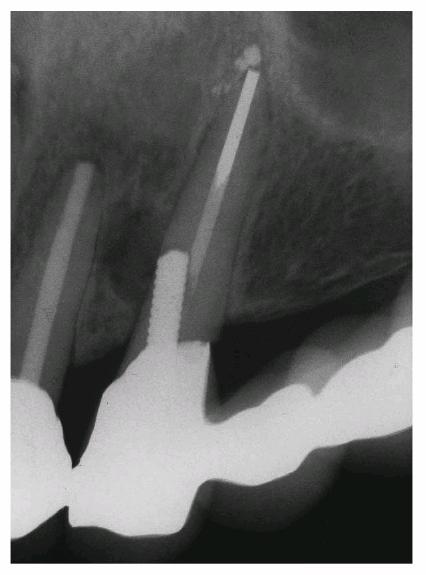

on both teeth (Figur 323s1823d es 18-7A

and B), the

Figur 323s1823d e 18-7A and B: Although this 12-year-old girl was referred to an oral surgeon for a postaccident extraction of both fractured central incisors, he wisely referred the patient to an endodontist in an attempt to save the teeth.

TREATMENT: Because saving teeth was a step-by-step procedure involving

endodontic treatment, periodontal surgery, and reconstructive techniques, the

treatment plan could be changed if one of the suggested treatments failed.

Endodontic therapy had already been completed on both central incisors. These

surgical procedures were performed next: removal of the tooth fragments that

were fractured vertically, labial and lingual gingivectomy and gingivoplasty,

palatal ostectomy, and labial frenectomy (Figur 323s1823d e 18-7C). Approximately 5 mm of palatal

plate was removed to expose new margins on the fractured teeth (Figur 323s1823d e 18-7D). After the tissue healed, gold

posts were constructed and cemented on the two maxillary incisors (Figur 323s1823d es 18-7E to

H). Final

preparations were made, and impressions for aluminous porcelain crowns were

made. The two crowns were seated (Figur 323s1823d es 18-7I

and J Figur 323s1823d e 18-7K is a radiograph of the teeth at the

end of treatment.